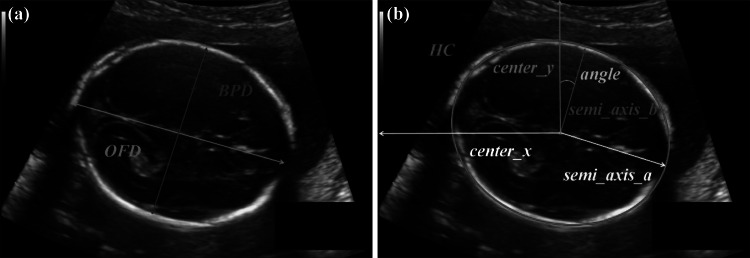

In clinical diagnosis, the measurement plane is the thalamus plane (the same as the measurement plane of BPD) when the fetal head is scanned. There are two commonly used estimation methods for fetal HC, as shown in Fig. 6. Method 1 (Fig. 6a) is based on occipitofrontal diameter (OFD) and BPD:

Fig. 6.

Two methods for fetal head circumference (HC) biometry. a Method 1: HC is calculated by measuring the occipitofrontal diameter (OFD) and biparietal diameter (BPD). b Method 2: HC is measured along the outer edge of the skull. Method 2 was used in this work

Method 1 has few measurement parameters and is easy to calculate. It is more accurate in the 12th to 28th week of pregnancy. However, in the early stage of pregnancy, there will be large deviation due to factors such as irregular shapes of gestational sacs and blurred skulls around the head. Therefore, at present, the ellipse fitting method, i.e., method 2 (Fig. 6b), is an important method for clinical measurement of fetal HC. The fitting position and size were determined according to the long axis (semi_axis_a), short axis (semi_axis_b), ellipse center point (center_x, center_y), and central angle (angle) of the fitted ellipse, as denoted in Fig. 6b. In method 2, HC was calculated by

In this paper, method 2 was used for HC biometric measurement.